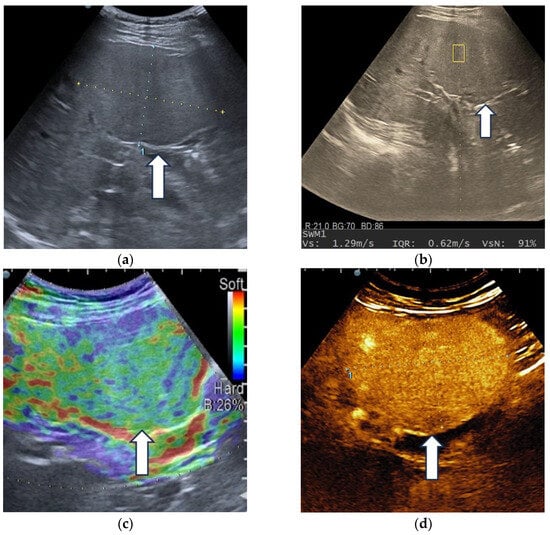

Figure 8.

Multiparametric ultrasound evaluation of a liver adenoma in a 60-year-old female patient. B-mode ultrasound showed an isoechoic homogenous focal liver lesion (arrow), with a size of 90/50 mm, located in segment IV (a). Shear wave velocity (Vs) obtained in the tumor was 1.29 m/s and the net amount of effective shear wave velocities (VsN) was 91%, suggesting a reliable measurement (b). In real-time transabdominal elastography, the lesion showed a mosaic appearance with predominant green areas (arrow), corresponding to type “b” elasticity (c). After intravenous administration of the contrast agent, diffuse homogeneous hyperenhancement (arrow) was observed (d), followed by sustained enhancement (arrow) during the late phase (e), even at 6 min after injection (arrow) (f).